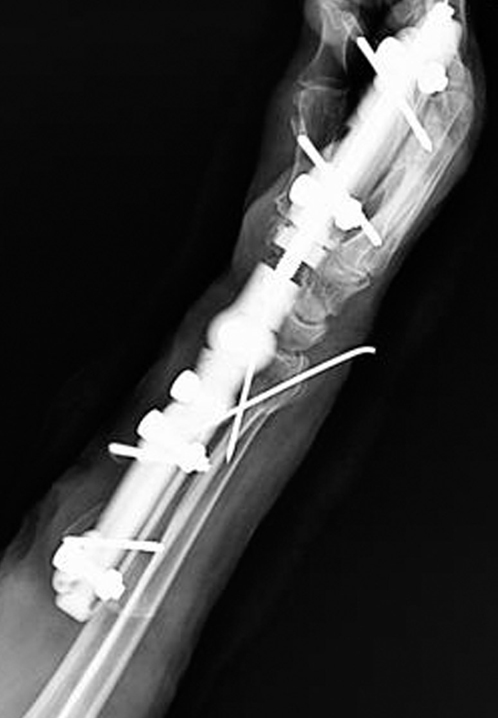

Dynamic Distal Radius

External Fixators

Concept

Distal radius fractures represent the most prevalent fracture type encountered in emergency settings. External fixation stands out as one of the optimal treatment modalities for managing distal radius fractures, particularly beneficial in cases involving articular or metaphyseal comminution.

Adjustment of the articular components of the external fixator is conducted in accordance with radiological parameters of the unaffected side.